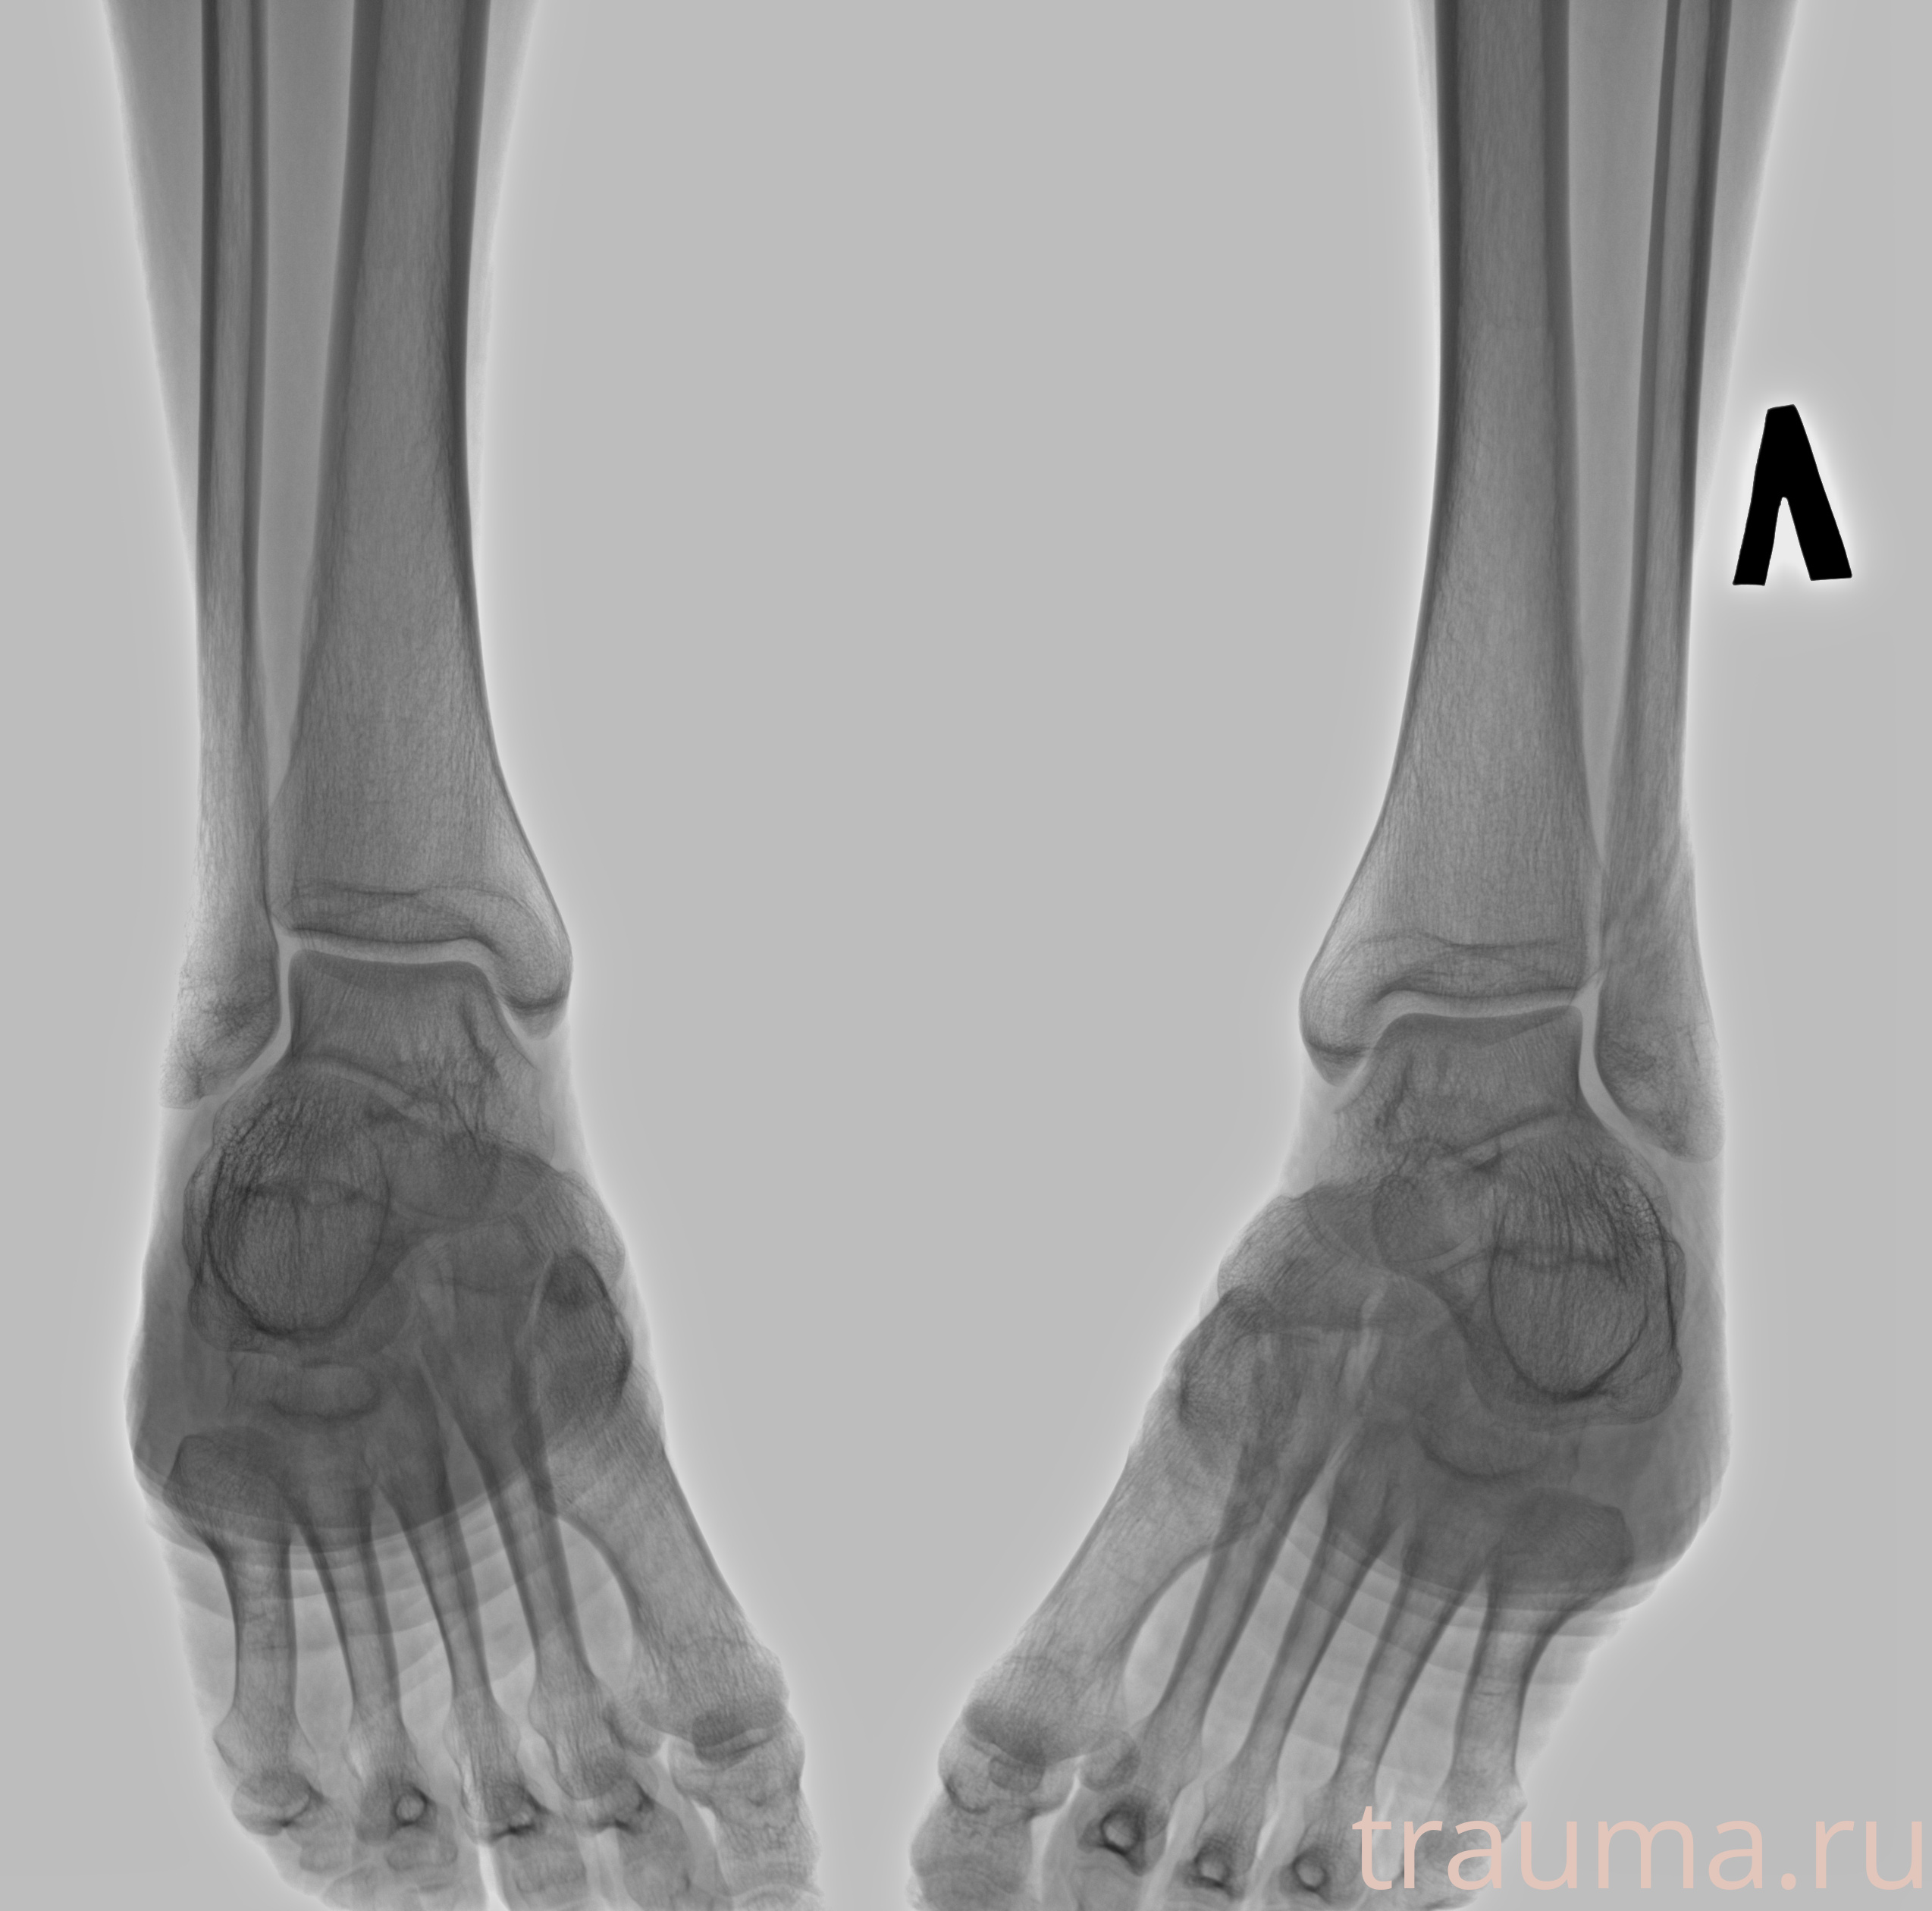

Рентгенограммы

Рентген на дому: по вашему адресу приезжает врач-рентгенолог, травматолог-ортопед с мобильным рентгеновским аппаратом, проводит диагностику травмы или заболевания, делает необходимые рентгенограммы, дает рекомендации по дальнейшему лечению. Получить качественные снимки в домашних условиях возможно благодаря уникальной методике, разработанной МосРентген Центром для института  Склифосовского